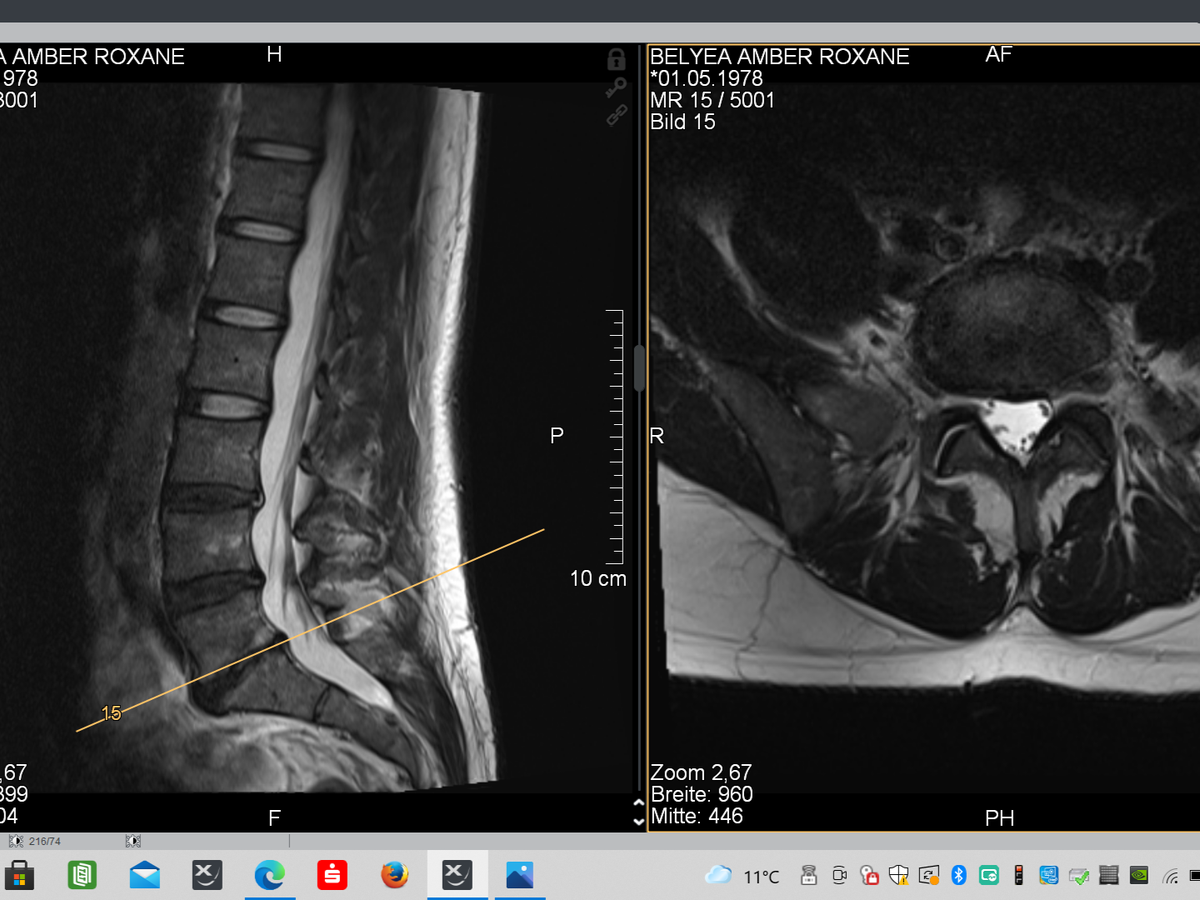

By chance this summer I met someone who's friend had been in the same situation as me that had went to Germany for surgery. I soon had a conversation with this person (who is now the Canadian liaison for ONZ) which then led to me sending my MRI results to the doctors at ONZspine.com in Germany. My treatment plan is to have a 3 level artificial lumbar disc replacement. These disc replacements are state-of -the -art disc that allows the joint in the spine once again to move in all 6 degrees of motion mimicking a healthy flesh disc. Without this surgery there could be further compression and result in irreversible neurological deficits. With this surgery the goal is to return to a fully active life style. The testimonies from people all over the world who have had these treatments speak for themselves.